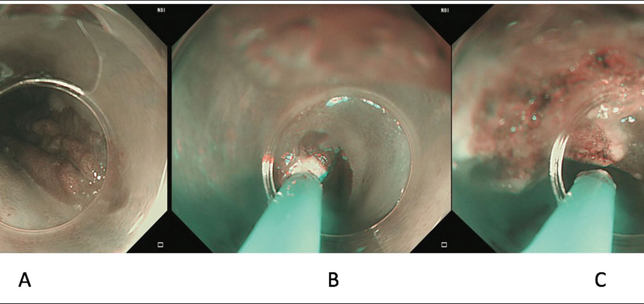

Dysphagia in complex laryngology – maintaining the balance